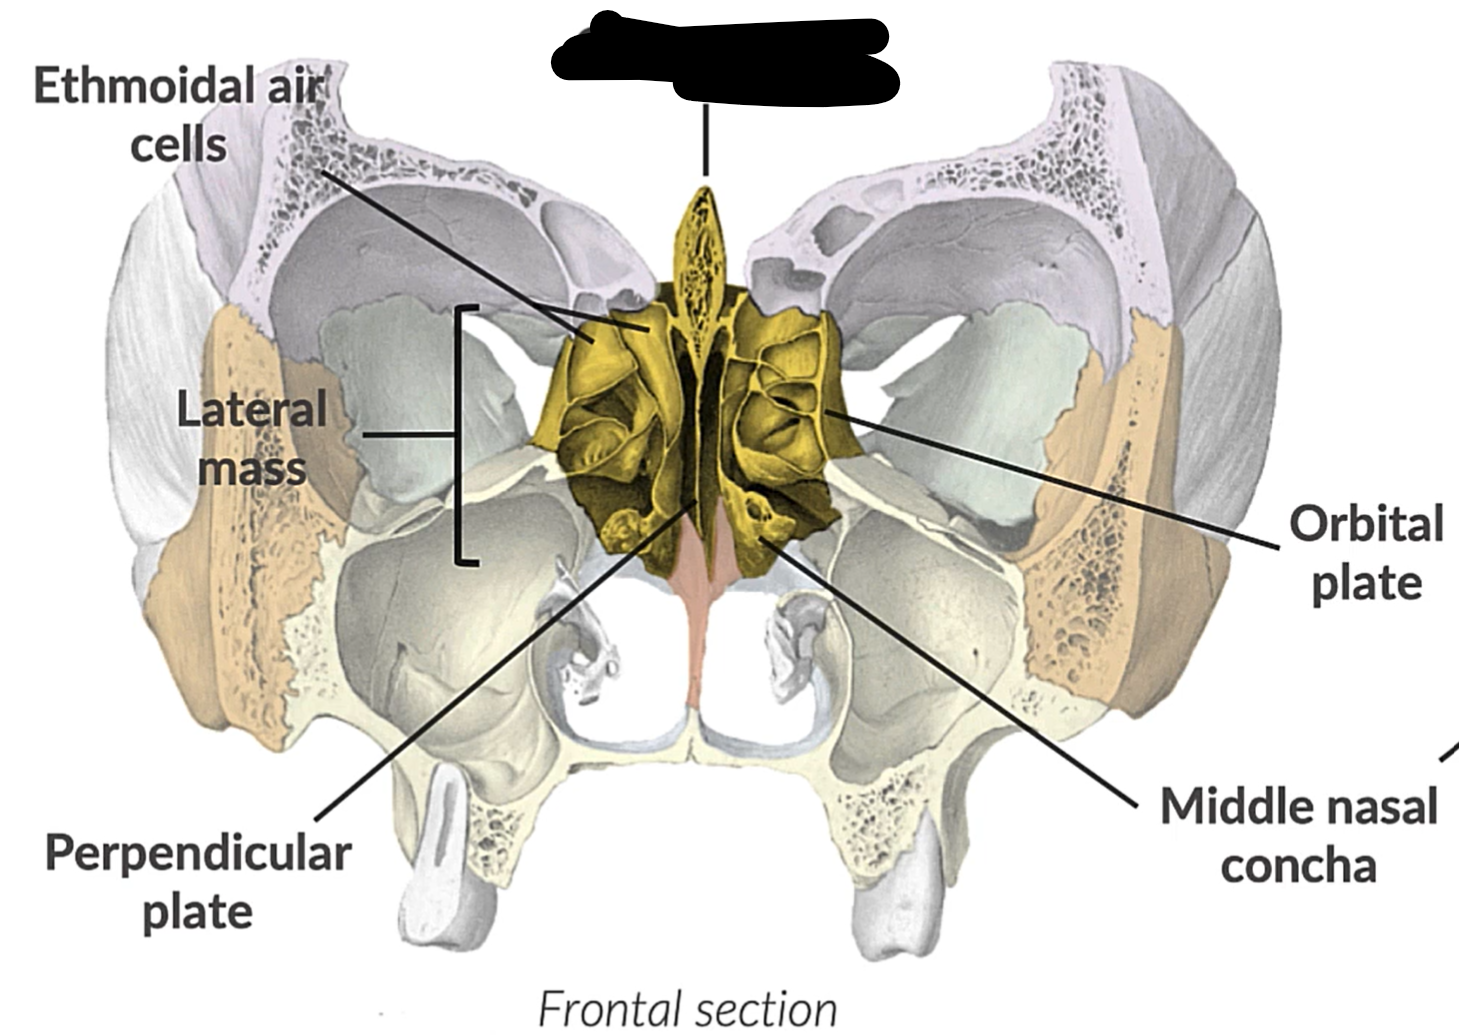

What bone is this?

Ethmoid bone

(NN)

Crista galli